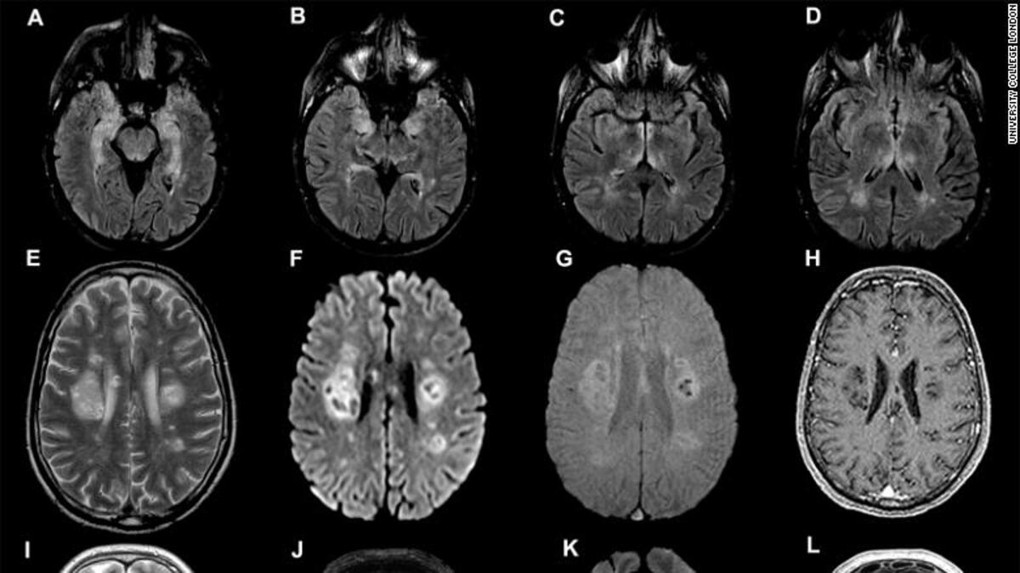

Nghiên cứu được thực hiện bởi Đại học College London (UCL), công bố hôm 8/7 trên Tạp chí Brain. Đây là công trình mới nhất nghiên cứu khả năng biến chứng, bao gồm đột quỵ, tổn thương thần kinh, viêm não gây tử vong ở người mắc Covid-19, ngay cả khi họ không có bất cứ triệu chứng hô hấp nghiêm trọng nào.

Trong số các bệnh nhân, 10 người bị "rối loạn chức năng não tạm thời" và mê sảng. 12 trường hợp khác bị viêm não. 8 người đột quỵ và 8 người tổn thương thần kinh.

Hầu hết bệnh nhân viêm não được chẩn đoán mắc một bệnh lý cụ thể, hiếm gặp là viêm não tủy cấp lan tỏa (ADEM). Biểu hiện lâm sàng gồm hội chứng thần kinh, mất hoặc giảm thị lực, liệt nửa người hoặc liệt tứ chi.

Trước đại dịch, nhóm chuyên gia ở London ghi nhận khoảng một bệnh nhân ADEM mỗi tháng. Trong thời gian nghiên cứu, con số đã tăng lên thành một người một tuần.